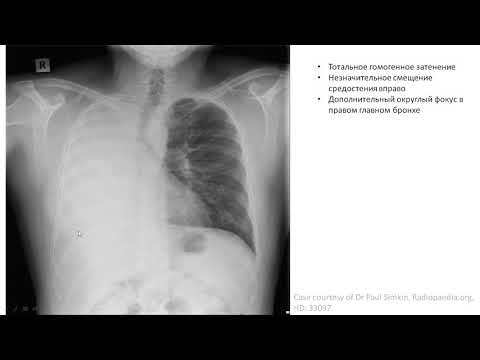

5 простых шагов для чтения рентгена легких